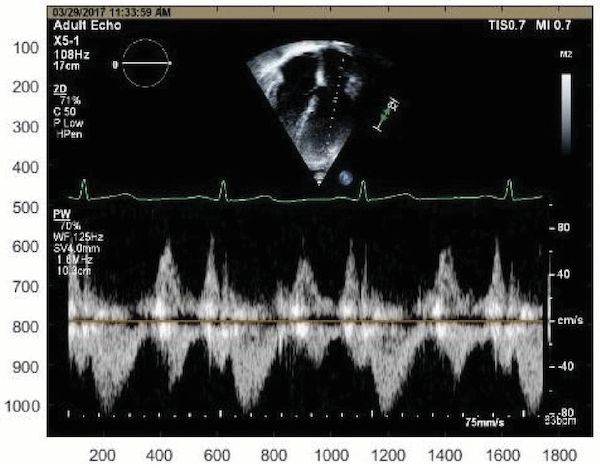

Taebi, A., Sandler, R.H., Kakavand, B., Mansy, H.A. (2019).

Extraction of Peak Velocity Profiles from Doppler Echocardiography Using Image Processing.

Bioengineering, 6(3): 64.

Taebi, A., Sandler R.H., Kakavand, B., Mansy, H.A. (2018).

Estimating Peak Velocity Profiles from Doppler Echocardiography using Digital Image Processing.

IEEE Signal Processing in Medicine and Biology, Philadelphia, PA.